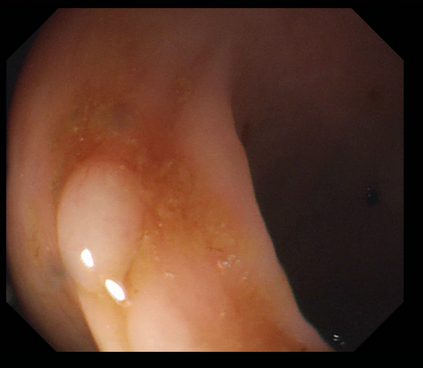

Deep learning has shown excellent performance in analysing medical images. However, datasets are difficult to obtain due privacy issues, standardization problems, and lack of annotations. We address these problems by producing realistic synthetic images using a combination of 3D technologies and generative adversarial networks. We use zero annotations from medical professionals in our pipeline. Our fully unsupervised method achieves promising results on five real polyp segmentation datasets. As a part of this study we release Synth-Colon, an entirely synthetic dataset that includes 20000 realistic colon images and additional details about depth and 3D geometry: https://enric1994.github.io/synth-colon